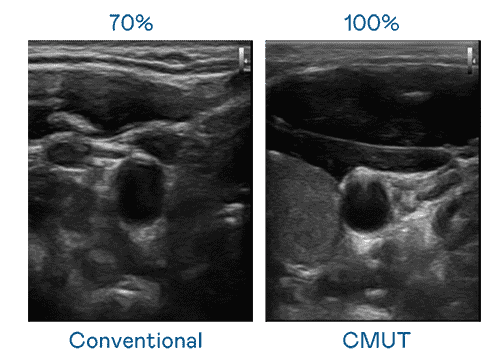

CMUT 技术是一种用电容式微机电元件来产生超音波讯号的技术。。。与传统 PZT 压电式技术相比,,CMUT 频宽增加 30%,,,,更宽频的超音波讯号让影像解析度大幅提升,,是实现高影像品质医疗超音波扫描、、、、促进精准医疗发展的关键技术。。。。

超音波影像的解析度高低,,,首先取决于探头能发出的讯号频宽。。。人生就是博 CMUT 可提供高清晰的超音波讯号,,,提供高频宽、、、高灵敏度、、、、影像纹理细节更高的超音波影像,,协助医护人员缩短影像判读时间及利用精准的医疗影像进行诊断。。